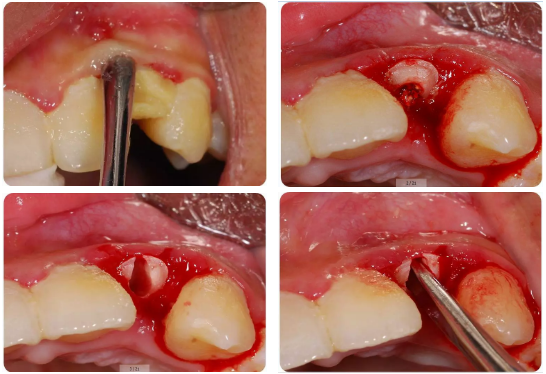

6、复杂的多根牙也可以“简单”拔除;

通过微创方法解决复杂的单根牙、多根牙

小断根处理的新思路和注意事项